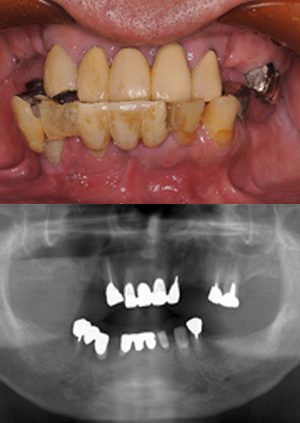

オールオン4症例③

1. all on 4③治療前

2. all on 4③治療後

主訴 被せものが取れた

治療内容 残っている歯は揺れていて義歯の使用に抵抗があるため、静脈内鎮静下にて上の歯を全てと下の奥歯を抜歯して上は4本、下は1本のインプラントを埋入。

上のインプラントは当日に固定式の仮歯を装着した。

骨とインプラントが結合するのをまち、最終的には上部構造を装着した。

治療期間 8か月

治療金額

• 静脈内鎮静費用:

¥88,000(税込)

• 上顎手術費用:

¥1,210,000(税込)

• 上部構造(チタンハイブリッドタイプ、噛む面はメタル)

• 下顎手術費用:

¥176,000(税込)

¥209,000(税込)